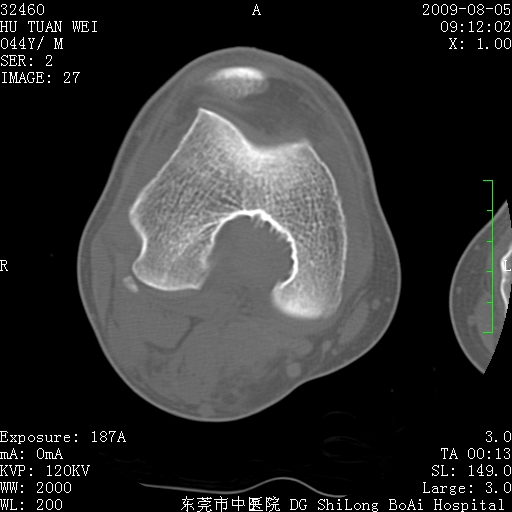

标题: CT21940:膝关节(有病理)

中年男性,膝韧带损伤术前检查!其他病史不清粗,不是我接手病人、且出院了!

1、股骨下段囊状膨胀性病变,边缘硬化明显,内多个残留骨棘呈多房型改变,囊腔密度较高无钙化,膝关节滑膜囊增厚,密度增高,关节腔少量积液。考虑:邻关节囊肿、退变性囊肿(软骨下囊肿)、着色性绒毛结节性滑膜炎、abc、骨巨、良性纤维组织细胞瘤等鉴。虽然年龄偏大,部位于骨端,但有外伤史,本人还是倾向于动脉瘤样骨囊肿(abc)可能性大。邻关节囊肿及软骨下囊肿次之考虑。

2、胫骨髁间棘撕脱骨折,交叉韧带损伤可能;

3、关节退行性改变。

病理结果:色素沉着绒毛结节性滑膜炎

感谢反馈病理结果!本病为慢性关节病变。以关节滑膜高度增生、绒毛结节形成伴含铁血黄素趁着为特点。病因:有炎症、肿瘤、外伤关节出血、代谢障碍、变态反应及感染等学说。增强扫描呈关节腔内单个或多个强化的软组织结节影或滑膜不规则增厚伴关节积液为本病的特征性表现。